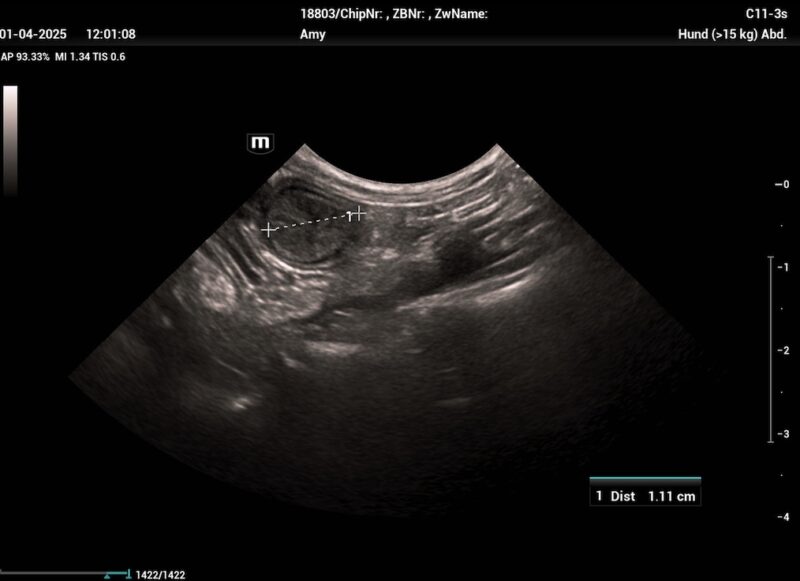

Es sollte immer eine (möglichst steril entnommene) bakteriologische Milchuntersuchung inkl. Antibiogramm eingeleitet werden. Weiters können eine Hämatologie und klinische Chemie bei Verdacht auf systemische Beteiligung (Leukozytose, Linksverschiebung, CRP ↑) und ein Ultraschall der Milchdrüse durchgeführt werden. Dieser zeigt bei einer akuten Mastitis nicht mehr von einander unterscheidbare Gewebeschichten. Die entzündeten Bereiche sind echoarm bis echolos und weisen eine grobkörnige Struktur auf. Das Gewebe ist stets heterogen. Bei einer gangränösen Mastitis zeigen sich Zysten mit echofreiem Inhalt und das Zentrum der Entzündung ist von jeglicher Blutzirkulation abgeschnitten (Trasch & Wehrend, 2008). Das Vorhandensein echoarmer, mit Flüssigkeit gefüllter Taschen im Brustgewebe deutet auf eine Abszessation des Brustgewebes hin, während ein hyperechogenes Parenchym auf eine chronische Mastitis hindeutet.